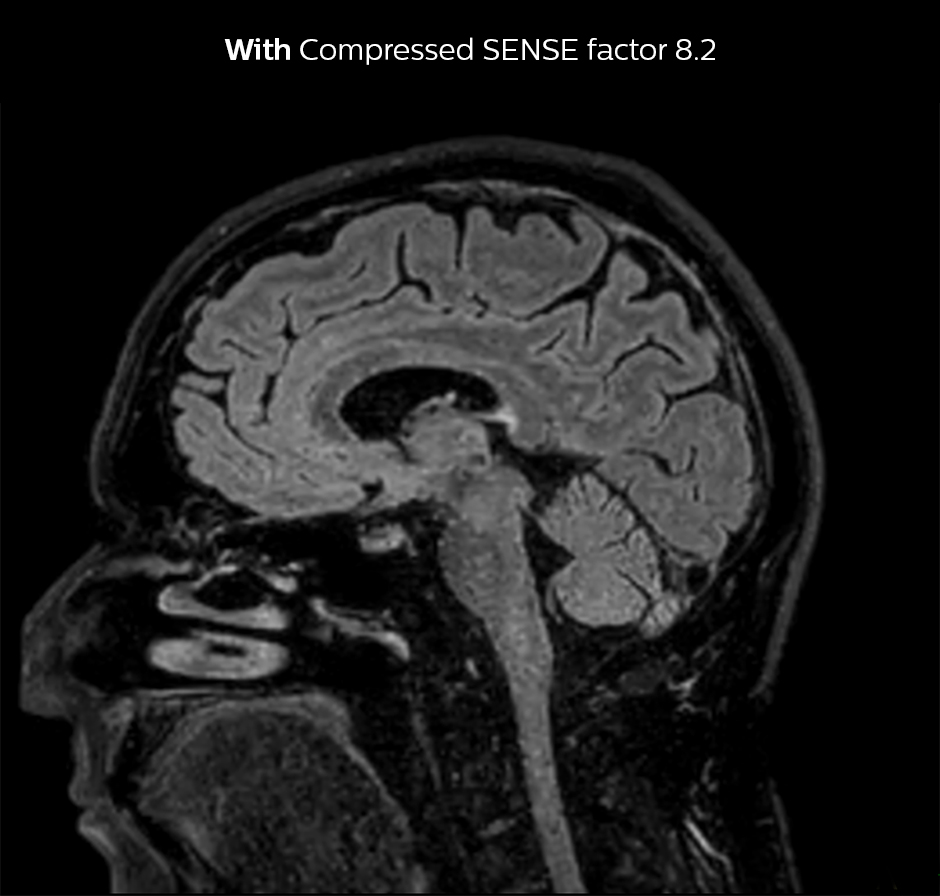

Shorter scan time in brain

Compressed SENSE allows 28% shorter scan time with the same spatial resolution.

3D FLAIR brain WITHOUT Compressed SENSE

3D FLAIR, scan time 5:02 min, voxel size 1.1 x 1.1 x 1.1 mm, Ingenia 1.5T.

3D FLAIR brain Compressed SENSE factor8

3D FLAIR, scan time 3:36 min, voxel size 1.1 x 1.1 x 1.1 mm, Ingenia 1.5T.